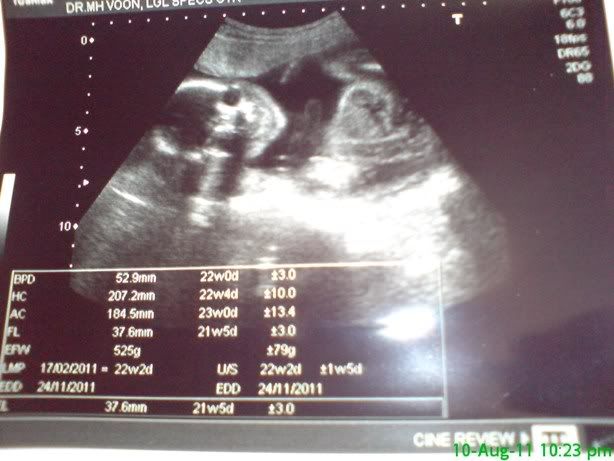

刚产检回来。。。。。医生说。。。是。。。。女儿。。。

上个月说可能是儿子,但这次看得比较清楚了,说 ...